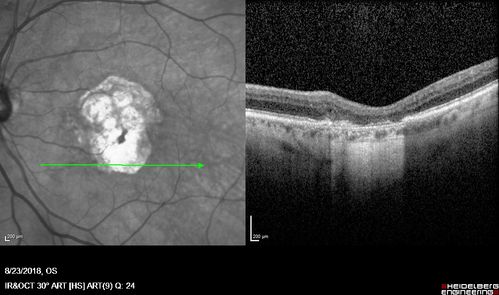

Outer Retinal Tubulation

78 year old man chronic wet AMD - 20/200

Outer Retinal Tubulation - Disciform Scar